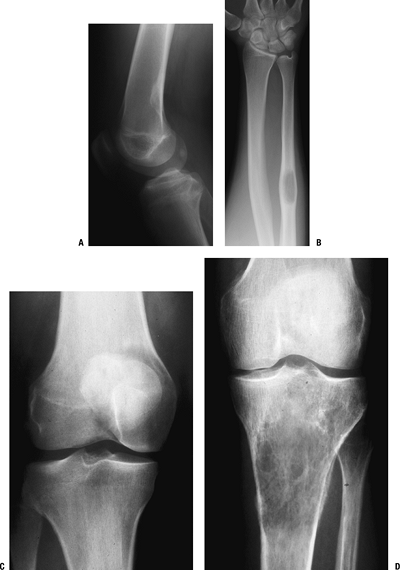

Benign tumors (Figs. 1-1 and 1-2)

-

Unicameral bone cyst

Nonossifying fibroma

Fibrous dysplasia

Malignant tumors (Figs. 1-3 and 1-4)

Osteosarcoma

Ewing sarcoma

Giant cell tumor (Fig. 1-5)

Figure 1-1 Pathologic fracture through unicameral bone cyst typically occurs without preceding pain.

Figure 1-2 Pathologic fracture through nonossifying fibroma typically occurs without preceding pain.

Figure 1-3 Pathologic fracture through an osteosarcoma is usually preceded by progressively worsening pain.P.9

Figure 1-4 Pathologic fracture through aggressive lesions such as this Ewing sarcoma is usually preceded by pain.

Figure 1-5 Pathologic fractures through giant cell tumors are usually preceded by pain, as was the case here.

Figure 1-6 Pathologic fractures through lesions created by metastatic carcinoma are often preceded by pain.-

Figure 1-7 Pathologic fractures through multiple myeloma lesions are often preceded by pain.